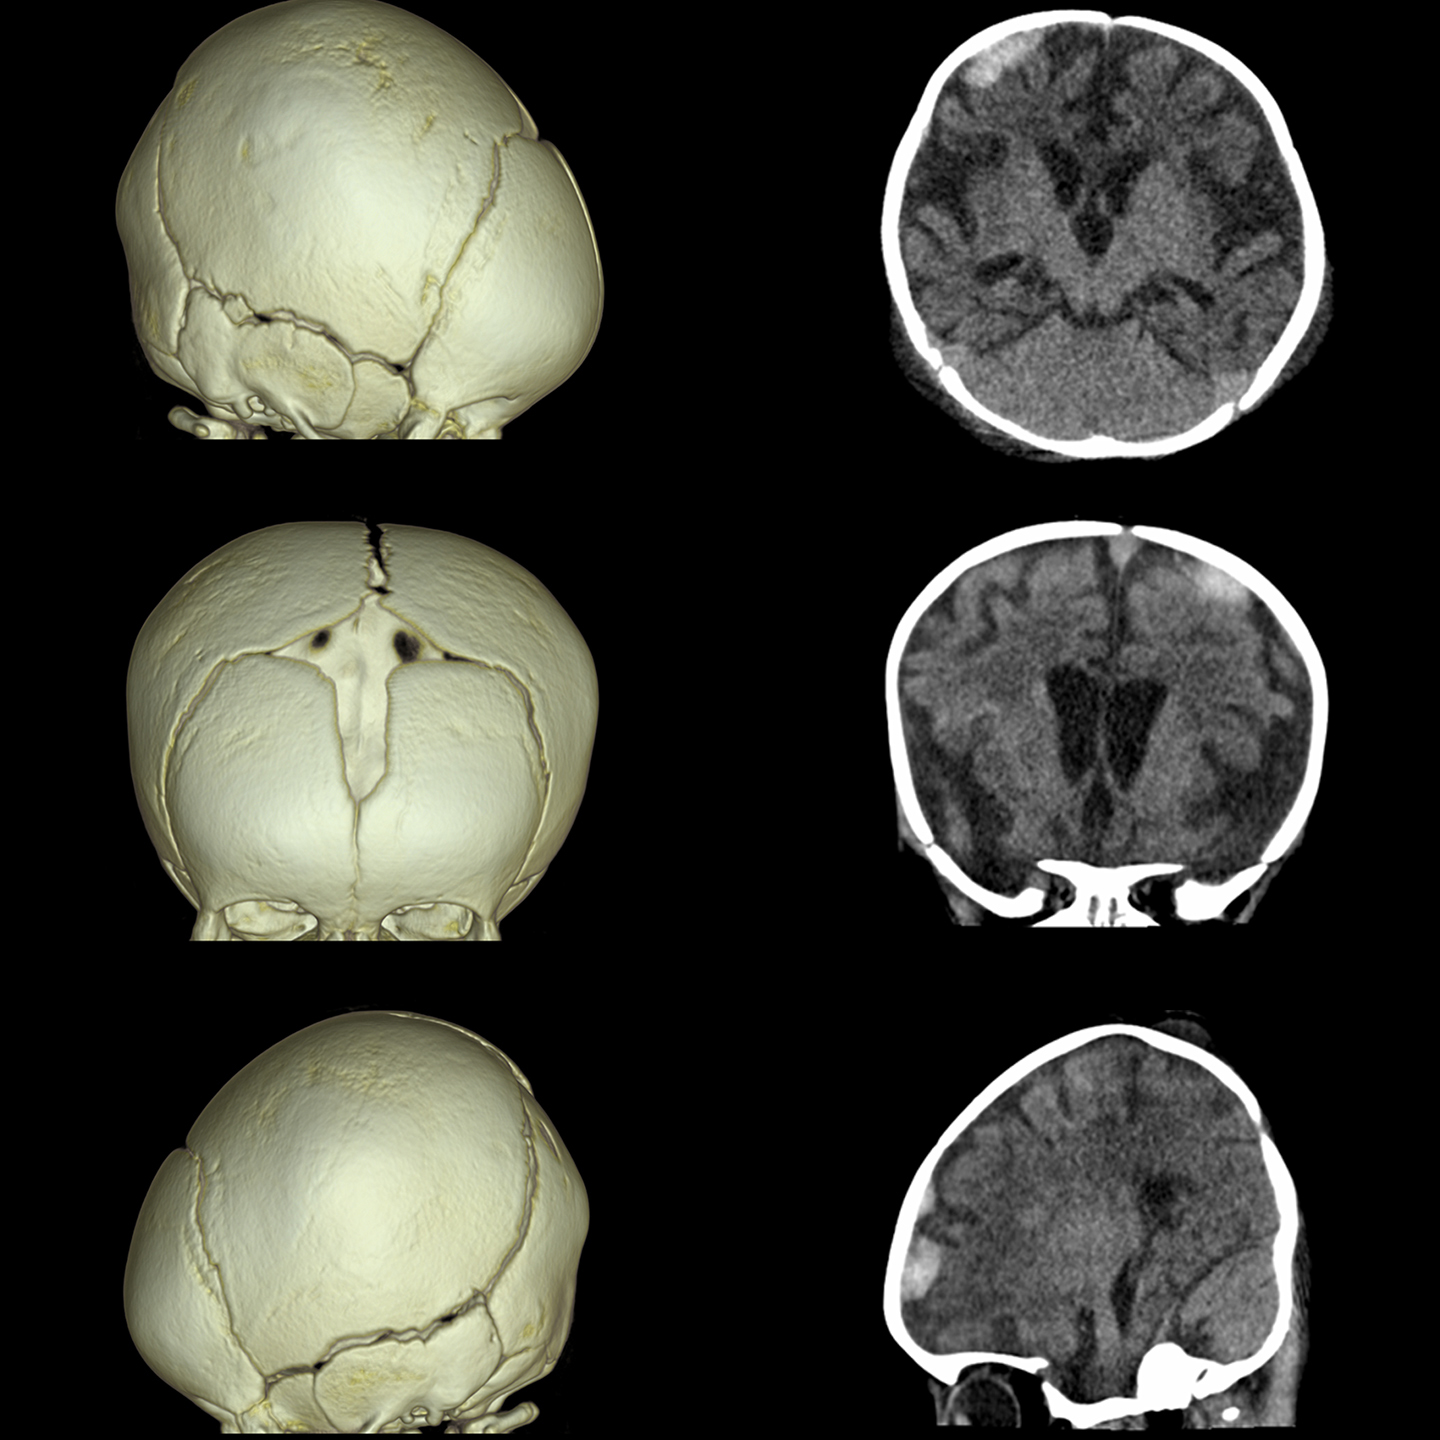

Фильтр SilverBeam

SilverBeam, энергетический фильтр, формирующий луч, использует свойства серебра по ослаблению фотонов для выборочного удаления фотонов низкой энергии из полихроматического рентгеновского луча, оставляя энергетический спектр, оптимизированный для скрининга рака легких.

КТ-скрининг рака легких при уровнях доз, приближающихся к обычной рентгенографии

Разработанный для работы в сочетании с AiCE, SilverBeam предоставляет улучшенные, высококачественные, малошумящие КТ-снимки скрининга рака легких при дозе облучения порядка типичного рентгенологического исследования грудной клетки.

SilverBeam с AiCE можно использовать для надежной организации службы скрининга рака легких в вашей больнице.